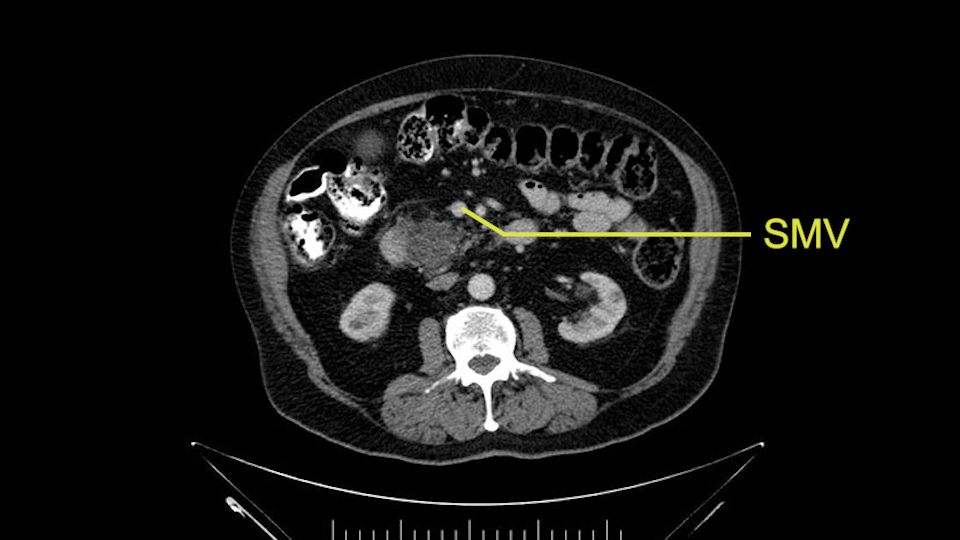

The next item that I would look at: the issue would be the vessels and usually start at the portal vein, watch the portal vein, follow it down, down-down-down to the neck of the pancreas - which is here - and there’s no impingement by tumor, which is great. The SMV and the splenic vein, which is here. The splenic vein junction is normal, which is great.

Then look at the first jejunal branch - which is this thing here - this little branch which goes under the SMA. It’s something that we’ve just started appreciating over the past few years and the reason for that is: there’s two or three small branches that come out of the uncinate into the the first jejunal and it’s a fairly inevitable part of the operation where there’s some bleeding. As long as you’re cognizant of what’s happening, it’s no reason to panic and that kind of bleeding will eventually stop or can be stopped but it’s not easy because these little vessels are fragile from the uncinate to the first jejunal. So I do focus on that and it’s pretty consistent I’d say 9 times out of 10, people have that first jejunal.

The initial hepatic flexure mobilization and the Kocher procedure is then going to enable me to understand the uncinate process of this patient, which should not be a problem, again. But the initial pictures had shown a degree of touching. I would not even say involvement or abutment; a degree of touching with the superior mesenteric vein. So that would give me an early chance to assess how the superior mesenteric vein is in this patient. So this would be the initial slowing down moment.